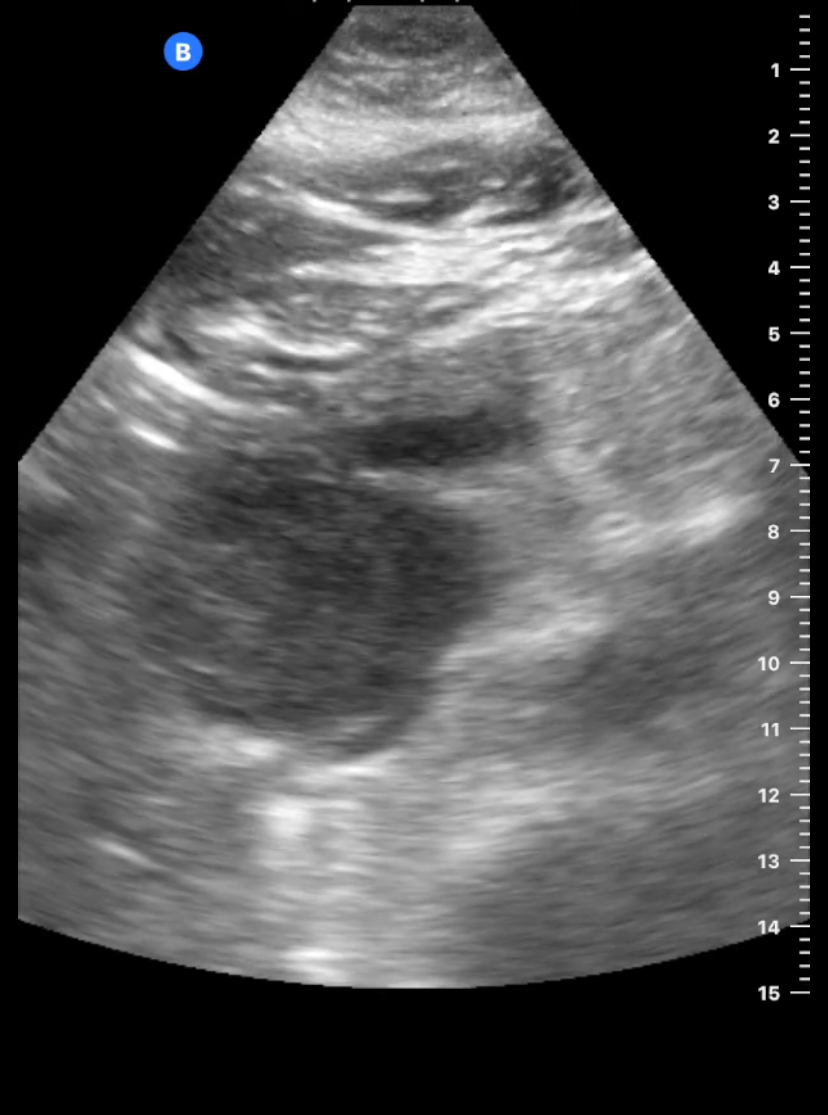

Paciente 1: vesícula con paredes muy engrosada, con contenido en su interior y empastamiento sugerente de abscesificación, derivada a urgencias y diagnóstico de colecistitis flemonosa.